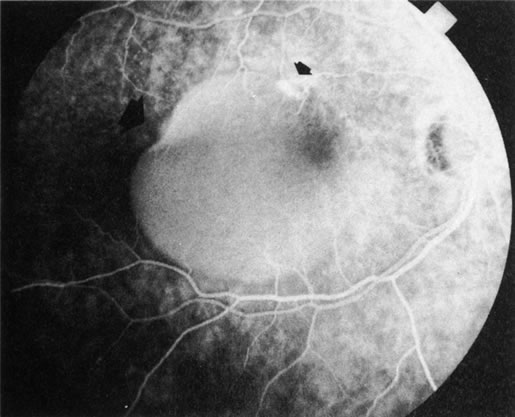

DIAGNOSIS Central serous chorioretinopathy (CSC) is characterized by breakdown of the outer retinal barrier, with leakage of fluid through a defect in the retinal pigment epithelium into the subretinal space, resulting in a serous neurosensory detachment.78–205 The ophthalmologist can usually diagnose CSC based on the clinical examination and demographic information.93–95 Most patients with CSC are middle-aged men74 who often have type A personalities.75, 96–104 CSC has also been associated to the use of corticosteroids,105–118 pregnancy,119–126 increased adrenaline level and stress,127–132 hemodialysis,133,134 collagen vascular diseases,135–147 and hypertension.148–157 CSC typically presents as a large serous detachment in the posterior pole without an obvious source of the subretinal fluid.76 However, because a small CNV cannot be ruled out, FA is usually done to confirm the diagnosis. Characteristically, there is a small RPE defect, which hyperfluoresces early, and then there is slow filling of the overlying neurosensory detachment, which may have a classic “smokestack” (Fig. 21) or “ink blot” (Fig. 22) appearance.158–161 Occasionally, FA demonstrates multiple sites of leakage (Figs. 23, 24, and 25). FA sometimes fails to distinguish CSC from CNV readily because fibrinous subretinal precipitates can cause slow filling of the RPE detachment, which is suggestive of CNV (Fig. 26). Sometimes peripapillary PCV can cause a neurosensory macular detachment masquerading as CSC (Fig. 27).77